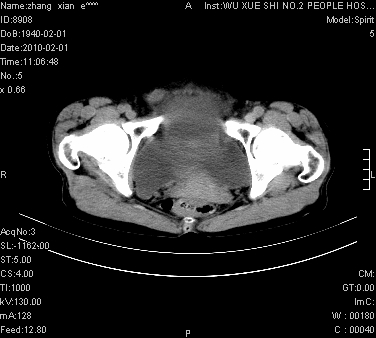

标题: CT24434:70岁 女 腹胀,腹水原因待查 [打印本页]

标题: CT24434:70岁 女 腹胀,腹水原因待查

大量腹水,脾脏囊性占位,子宫颈占位,右侧腹股沟淋巴结肿大,建议+c,先查妇科。

腹盆腔大量积液,子宫增大,子宫颈增大外形不规则,内见低密度影,膀胱后壁显示不清,右腹股沟肿大淋巴结,脾脏囊性占位,子宫颈占位,子宫颈癌?建议增强。